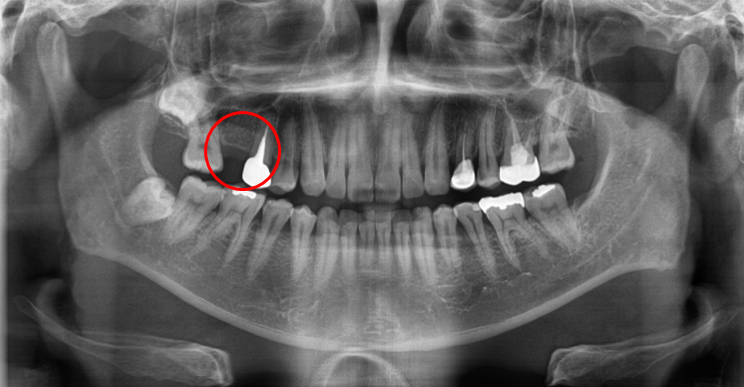

치료 전 : BRFORE

청담역치과 2021-07-22

치료 전 사진입니다.

십 년 전, 딱딱한 음식을 먹다가 치아가 상실하였다고 합니다.

그동안은 크게 불편하지 않아 빠진 것도 잊고 지냈는데

양옆의 치아가 점점 비어있는 공간으로 기울고 있다는 느낌이 들고 음식물을 씹을 때도 점점 불편하셨다고 합니다.